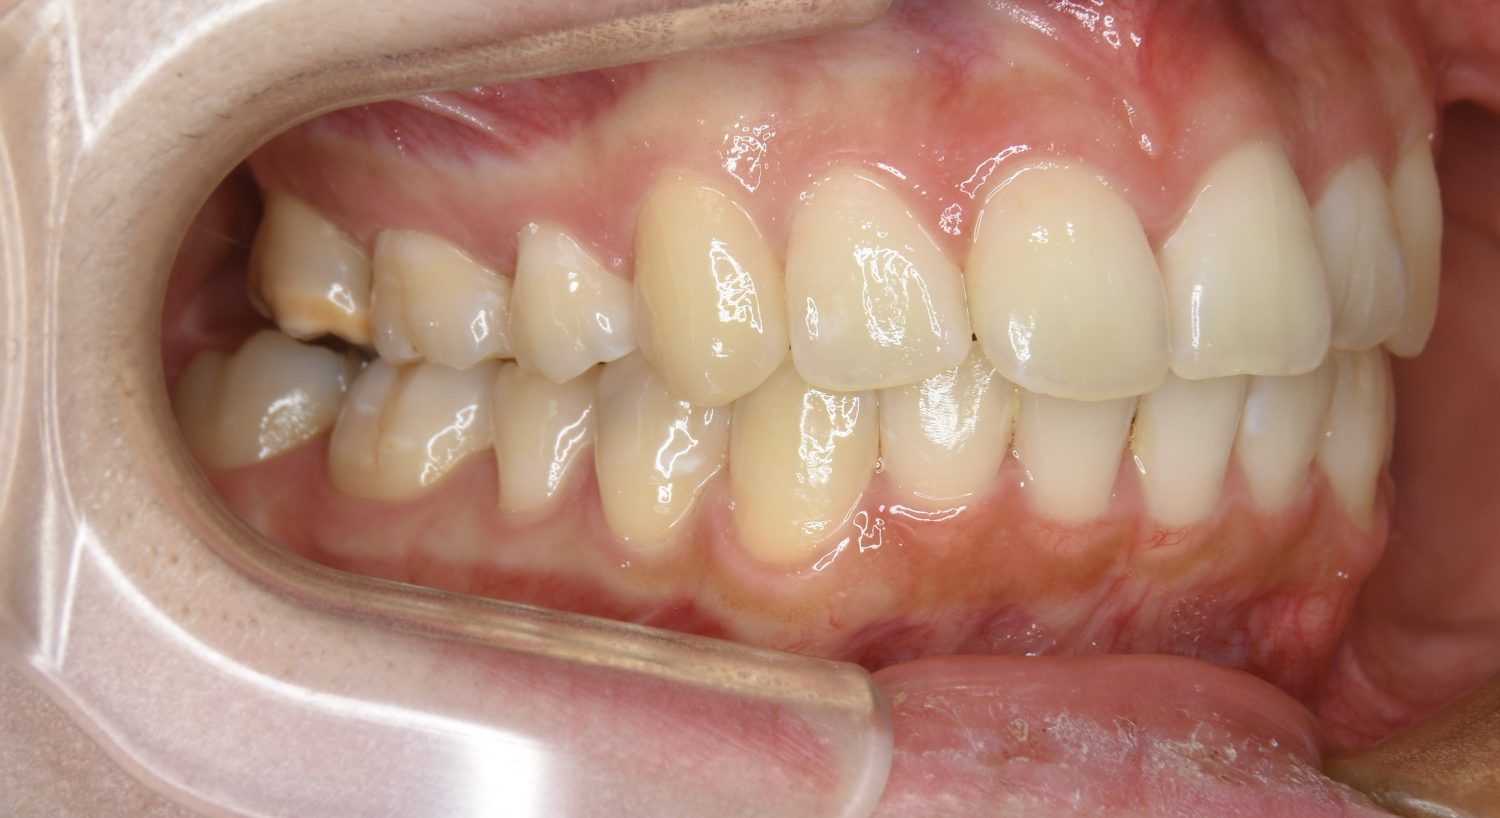

上顎前突の症例紹介①

Before

After

主訴

上の歯が出ている。歯並び全体が気になる。

治療内容

上顎両側第一小臼歯を抜歯し、上下ラビアルブラケット(唇側装置)に矯正用アンカースクリューを併用し治療を行いました。

治療費

1,000,000 円(税込)

治療期間

26ヶ月

通院回数

25回

想定されたリスク

※なし

丸山和宏先生

ピーススマイル矯正歯科

上顎前歯の前突により口元の突出が認められました。上の左右の第一小臼歯を抜歯し上顎前歯を後退させることで口元の突出感は改善し、咬合も良好な状態となりました。